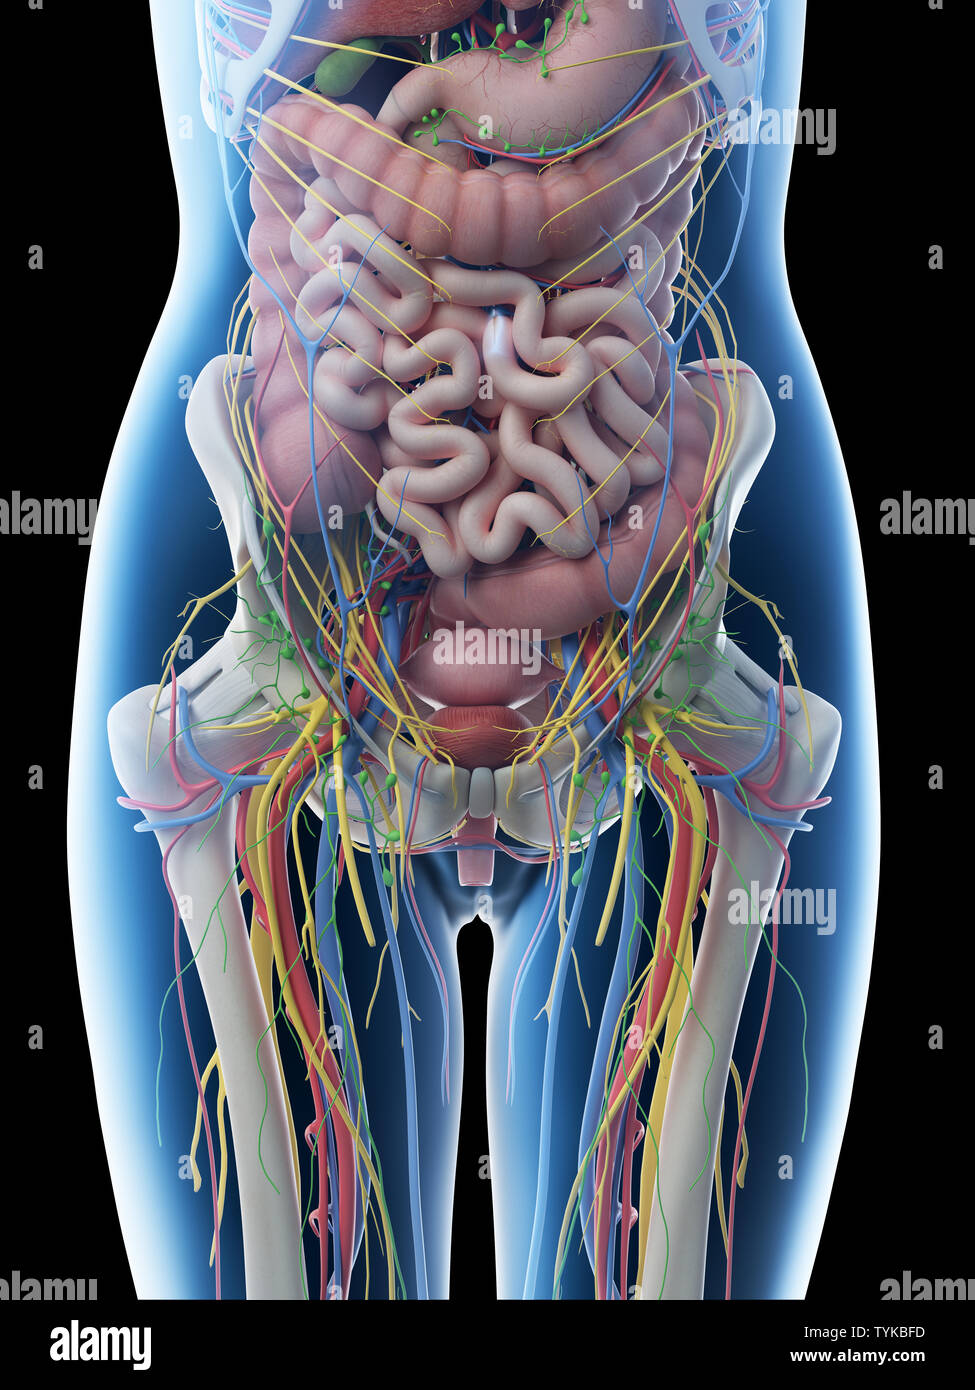

anatomychart101.storage.googleapis.comIllustration Of Human Abdominal Anatomy In Body Silhouette. — Digitally

anatomychart101.storage.googleapis.comIllustration Of Human Abdominal Anatomy In Body Silhouette. — Digitally

www.wallpaperflare.com3d Rendered Illustration Of A Females Abdominal Anatomy Stock Photo - Alamy

www.wallpaperflare.com3d Rendered Illustration Of A Females Abdominal Anatomy Stock Photo - Alamy

www.alamy.comanatomy 3d abdominal female illustration alamy females rendered

www.alamy.comanatomy 3d abdominal female illustration alamy females rendered